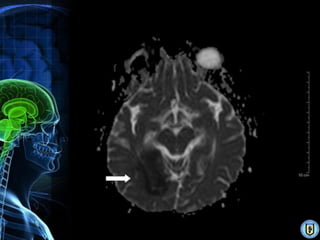

Diagnóstico

•   RMN (mejor para AVC isquémico)

•   Angiografía cerebral (Gold Standard)

•   TAC. (isquémico & hemorrágico)

•   Doppler transcraneal.

• 20.

Diagnóstico • RMN (mejor para AVC isquémico) • Angiografía cerebral (Gold Standard) • TAC. (isquémico & hemorrágico) • Doppler transcraneal.